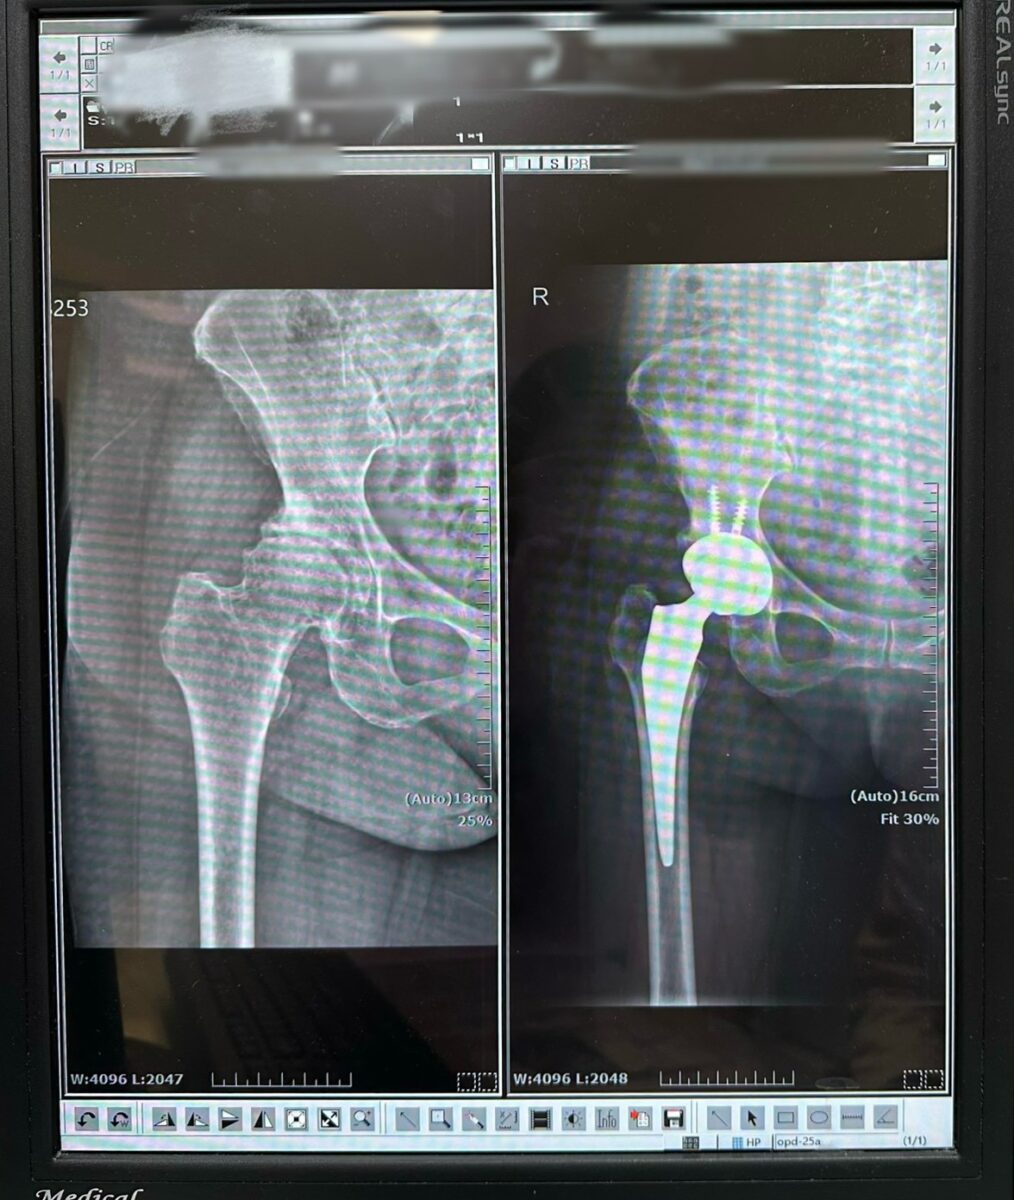

▲楊女士的人工髖關節置換前後的X片對照。

賴醫師指出,正前開人工髖關節置換術如同「撥開門簾進入室內,而非拆門而入」,所以肌肉與肌腱得以完整保留,患者在術後初期即可感受到行動負擔減輕,對於提升復原速度與生活品質具有明顯助益,此外,正前開手術在精準度上也具優勢。醫師透過術中 X 光即時導引,確保人工關節置放於最佳位置,有效降低術後出現長短腳的風險。由於周邊肌肉包覆良好,患者術後對於姿勢與動作的限制相對較少,更有利於回歸日常生活。